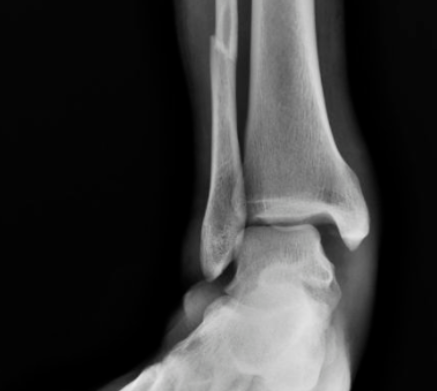

后踝骨折及下胫腓联合螺钉取出时机与下胫腓不稳的关系

对合并下胫腓联合损伤的内外踝骨折或三踝骨折,常规置入下胫腓螺钉,同时为避免螺钉断裂,恢复下胫腓微动,术者常规在术后6-8周或术后3月取下胫腓螺钉,但下胫腓螺钉取去存在下胫腓不稳风险。为研究双踝/三踝骨折下胫腓螺钉取出的最佳时机,及未固定的后踝与下胫腓稳定性的关系,有学者进行了相关研究,结果发表在近期Injury期刊上。